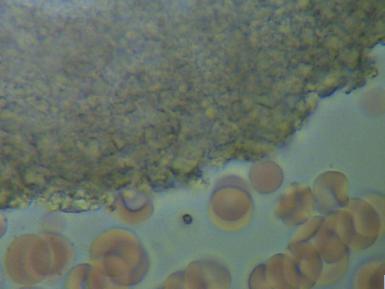

2.PASOŻYTY I GRZYBY

w zakwaszonym środowisku rozwijają się różnego rodzaju organizmy pasożytujące : robaki, grzyby, bakterie, wirusy i inne. Walka z nimi jest możliwa tylko przez zmianę środowiska z kwaśnego na zasadowe, w tym środowisku nie mogą się one rozmnażać i żyć.

We krwi widoczne są larwy i jaja pasożytów.

Komórki grzybów. W zależności od tego w jakim stopniu organizm zaatakowany jest przez grzyba widoczny jest obraz pojedynczych komórek lub całych kolonii i wtedy możemy mówić o bardzo niebezpiecznej dla organizmu grzybicy.